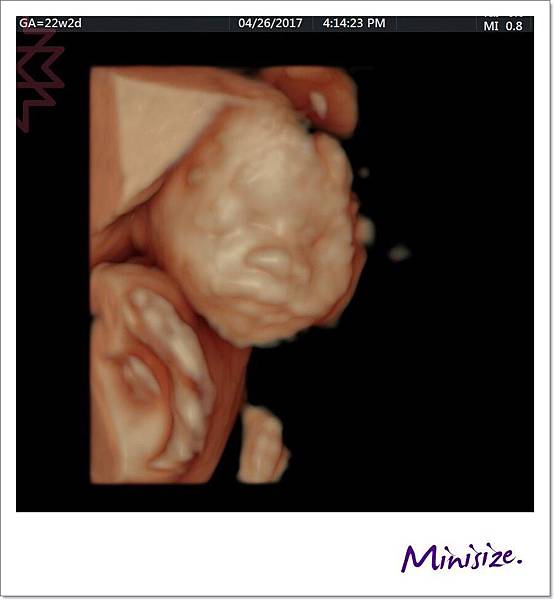

面

一直很期待看到寶寶的長相

究竟是像爸爸還是麻麻?!

爸媽綜合體又會呈現什麼樣子

也許寶寶想保留一點神祕感

這是唯一張好好配合拍照的

大大的鼻子、嘴巴好福氣!!

還記得前面提到 會有兩次醫療人員操作儀器檢查嗎?

技術師只捕捉到一張寶寶正面照

其他因寶寶姿勢的關係

技術師交棒給醫生的時候也有特別註明

醫生快速地全項目檢查一輪後

將之前未完成的部分也足一補齊

我們又再度回到胎兒的正臉

此時寶寶跟我們玩起遊戲來了

頑皮寶寶:手手、 臍帶 一起遮住臉臉不給你們看